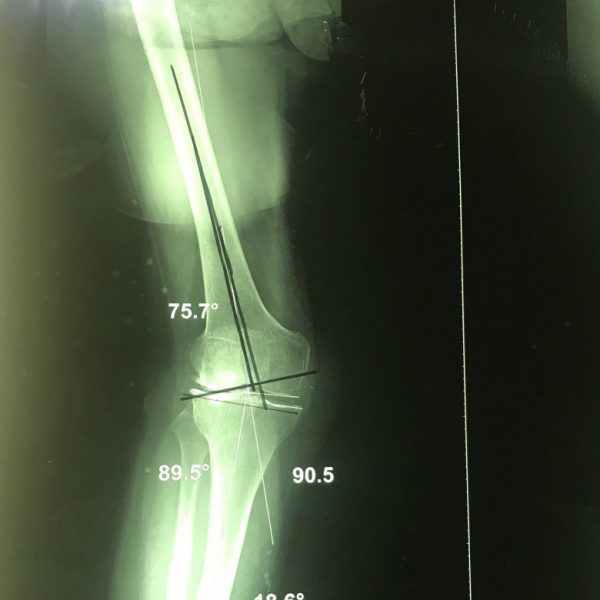

Braket diz sapması

Dizliklerin diz üstünden sapmasının düzeltilmesi. Bazı durumlarda yapılır ve bu hastalarda, yaygın vakaların aksine, dizin femurdan sapmasının nedenidir. HastaIranianProblemdizlikreferansOcak 2024TeşhisDizTedaviAmeliyat ... Read More